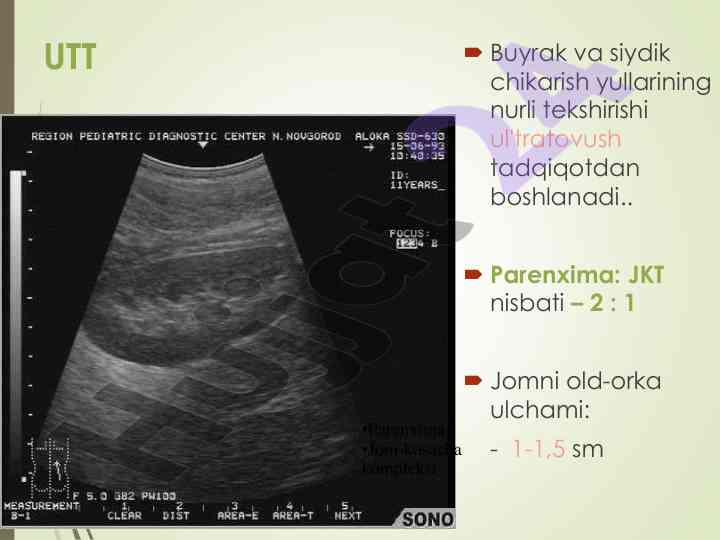

Buyrak va siydik yo'llarini nurli tekshirish usullari

Siydik tizimida rentgenologik metodlar yordamida diagnostika jarayonlari, ularning afzalliklari va ko'rsatmalari to'g'risida ma'lumot.